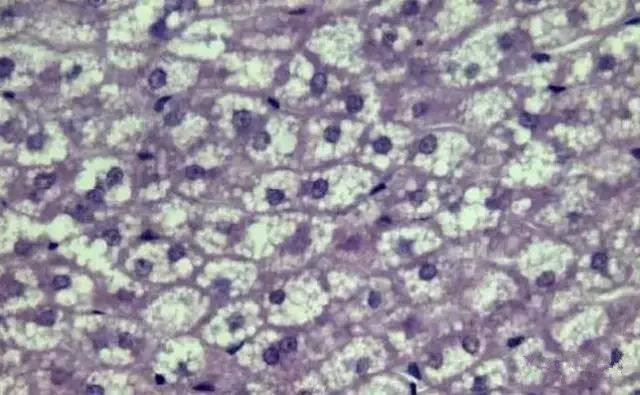

“ 脂肪变性

“ 正常鲤鱼肝胰脏